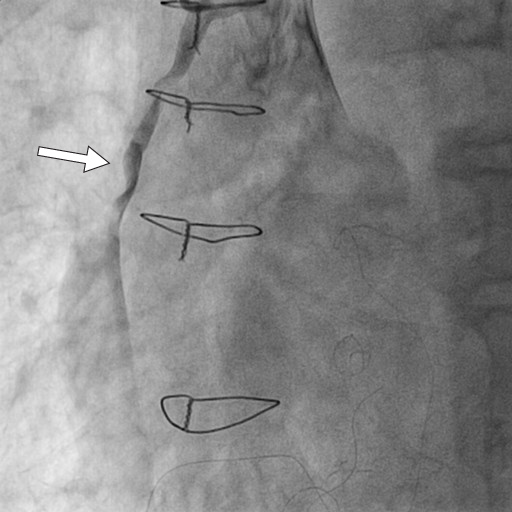

We present a case of a 79 years old male, with CABG intervention 12 years ago, admitted with inferior STEMI, 5 hours from onset. At that time, the patient was in a critical condition, presenting acute pulmonary edema and impaired ventricular rhythm in the form of sustained ventricular tachycardia. The coronary angiography demonstrated chronic total occlusions (CTO) of both native vessels (Figure 1, 2), functional bypass at the left anterior descending artery (LAD) level with left interior mammary artery (LIMA) (Figure 3), the absence of circumflex artery bypass, and acute thrombotic occlusion of the saphenous vein grafts (SVG) bypass for right coronary artery (RCA) (Figure 4).

Figure 3. Permeable left interior mammary artery (LIMA) (arrow) to left anterior descending artery (LAD).